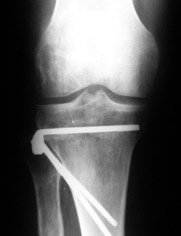

Mangal Parihar 11 Сентябрь 2005, 11:28

|

Alex,

I do upper tibial osteotomies with either an ilizarov fixator and acute correction of the deformity or with an orthofix with gradual correction.

Sending you pics of the steps of the osteotomy and the frame.

You can do the osteotomy in a "focal dome" or in a transverse fashion. The dome has the advantage of having a good contact, allowing weight bearing as tolerated early on.

The level is below the tibial tuberosity.

The frame I use is pretty simple, with one wire each in the proximal and distal ring, two schanz pins in the proximal ring, and one each in the middle and distal ring.

I preconstruct a frame with the proximal ring in varus by the use of coupled washers in the threaded rods in the front and back. These are used as hinges, and after the correction, a medial and lateral threaded rod is also added.

Since the center of rotation of these deformities is usually near the knee joint line, lateral translation of the distal fragment is necessary to normalise all the axes.

You can also do the osteotomy in a transverse fashion.

When I use an orthofix fixator, the osteotomy is oblique, starting below the tuberosity and ending 1 cm away from the lateral cortex at the level of the head of the fibula. No fibular osteotomy is needed there. The deformity is gradually corrected over 2 or three weeks.

You could also do the same with an ilizarov fixator

Regards

Отправитель: Alexander Artemiev 11 Сентябрь 2005, 14:55

Приветствую.

MP> I do upper tibial osteotomies with either an ilizarov fixator and

MP> acute correction of the deformity or with an orthofix with gradual

MP> correction.

Посмотрел я картинки:(

Это не эстетика.

Это рубка леса и лучевая болезнь.

С уважением Александр Артемьев